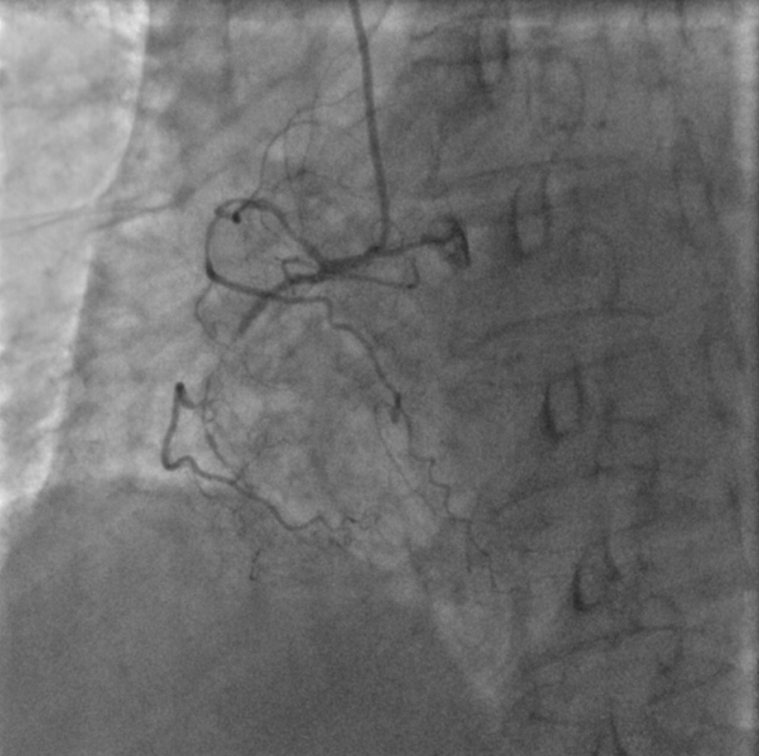

、慢性肾功能不全、双侧髂动脉曾植入支架。1月前外院冠脉造影提示三支血管均有重度钙化,左前降支(LAD)中段狭窄90%、对角支(D)狭窄80%、左旋支(LCX)近段狭窄90%、右冠状动脉(RCA)中段次全闭塞、远端慢性闭塞(视频1,图2-5)。

复查冠脉造影显示RCA同侧侧支消失,RCA侧支几乎全部由对侧LAD通过间隔支和心尖部提供(视频11,图12)。